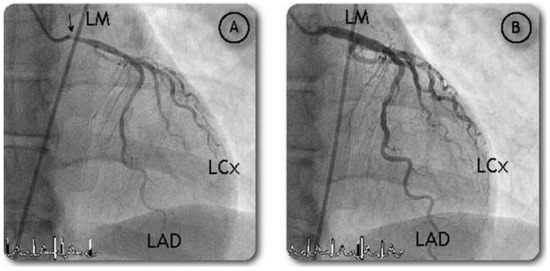

Cold Hands, Headache and Chest Pain: A Winter Disease?

by Igal Moarof, Ulrich Ingold and Stéphane Cook

Cardiovasc. Med. 2007, 10(7), 262; https://doi.org/10.4414/cvm.2007.01257 - 24 Aug 2007

A 57-year-old woman was scheduled to undergo elective invasive coronary angiography after having recurrent chest pain on exertion during the last four winter months [...] Full article

Show Figures

Figure 1